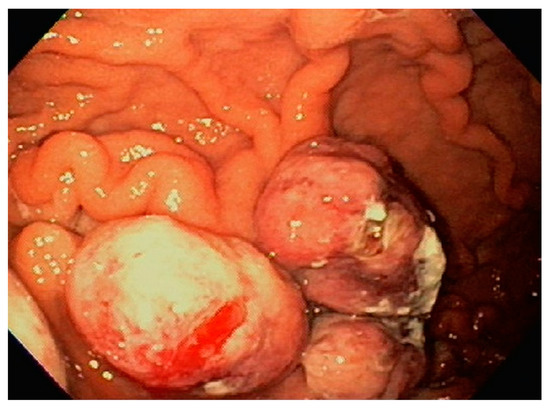

| 4 | F | 73 | Kidney | Fundus and body | Multiple large friable masses | Liver and lungs | Clear cell renal carcinoma | Nephrectomy, chemotherapy, immunotherapy (Axitinib) | Death 10 days after EGD diagnosis of metastasis |

| 5 | M | 76 | Lung | Body | Cratered ulcers | Liver, bone and adrenals | Small cell carcinoma (poorly differentiated neuroendocrine Ca) | None | Death 7 days after EGD diagnosis of metastasis |